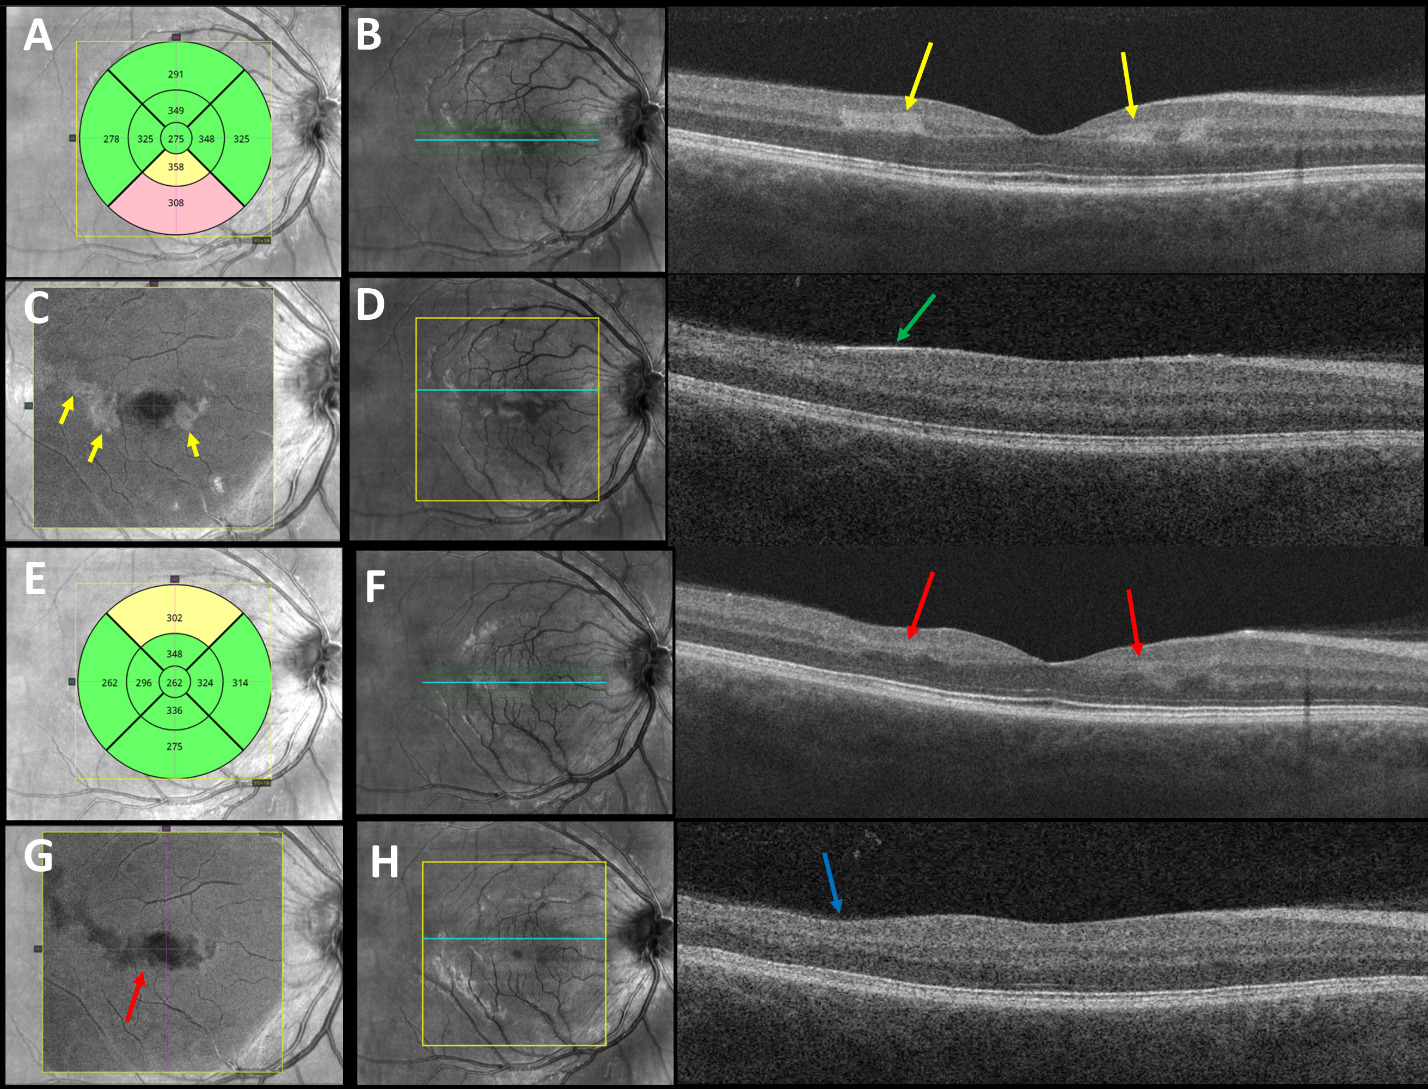

Best-corrected visual acuities were 20/20-1 right eye and 20/20-1 left eye. Pupils were equally round and reactive to light without an afferent pupillary defect. Extraocular movements were smooth and full in both eyes. Confrontation visual fields were full to finger counting in each eye. Amsler grid testing revealed a small area of metamorphopsia temporal to fixation in the right eye and small areas of metamorphopsia nasal and superotemporal to fixation in the left eye. Red cap testing was equal between the eyes. Slit lamp examination of the anterior segment was unremarkable in both eyes. Intraocular pressures by Goldmann applanation tonometry measured 14 mm Hg in each eye. Dilated fundus examination revealed a cup-to-disc ratio of 0.25 in each eye with well-perfused neural retinal rim tissue without edema or pallor. Examination of the posterior pole revealed mild retinal whitening superotemporal to the fovea in both eyes, a cotton wool spot in the inferior nasal arcade and a cotton wool spot in the inferior temporal arcade of the right eye, and 2 cotton wool spots in the superior temporal arcade of the left eye (Figure 1). The arterial-to-venous ratio was 2/3 in both eyes with no vascular tortuosity and no visible emboli. The peripheral retina was flat without holes, tears, or breaks in both eyes. Optical coherence tomography of the retinal nerve fiber layer revealed thick retinal nerve fiber relative to the normative database (not indicative of subclinical edema but rather due to his young age) inferiorly and nasally in both eyes with average retinal nerve fiber layer thickness of 127 microns in the right eye and 123 microns in the left eye (Figure 2). Optical coherence tomography showed central subfoveal thickness of 275 microns in the right eye (Figure 3A) and 271 microns in the left eye (Figure 4A). There were parafoveal hyperreflective bands in the inner nuclear layer worse in the right eye (Figure 3B) compared with the left eye (Figure 4B). En face optical coherence tomography at the level of the mid-retina showed patchy hyperreflectivity worse in the right eye (Figure 3C) compared with the left eye (Figure 4C), which corresponds to the inner nuclear layer hyperreflectivity on cross-section. Interestingly, in this case, there is also hyperreflectivity of the internal limiting membrane superotemporal to the fovea in both eyes (Figures 3D and 4D, right and left eye, respectively) that corresponds to the areas of retinal whitening seen on fundoscopy. The superficial capillary plexus on optical coherence tomography angiography showed an abnormal foveal avascular zone with small patches of capillary dropout worse in the left eye (Figure 5C) compared with the right eye (Figure 5A); the deep capillary plexus showed multifocal ovoid areas of signal attenuation due to capillary dropout in both eyes (Figures 5B and 5D, right and left eye, respectively).

He was monitored at 4-week intervals but was lost to follow-up after the 3-month visit. Visual acuity improved to 20/20 in each eye at the 1-month follow-up and remained stable throughout the clinical course. Despite this, small areas of metamorphopsia paracentrally worse in the left eye compared with the right eye persisted on Amsler grid testing. Humphrey visual field 10-2 Swedish Interactive Thresholding Algorithm Standard was performed at the 2-month follow-up and confirmed paracentral defects worse in the left eye than in the right eye (Figure 6). At the 3-month follow-up, there was resolution of the retinal whitening and cotton wools spots and near resolution of the paracentral acute middle maculopathy. Optical coherence tomography showed central subfoveal thickness of 262 microns in the right eye (Figure 3E) and 252 microns in the left eye (Figure 4E). There was parafoveal inner nuclear layer thinning worse in the right eye (Figure 3F) compared with the left eye (Figure 4F). En face optical coherence tomography at the level of the mid-retina showed multifocal patchy hyporeflectivity worse in the right eye (Figure 3G) compared with the left eye (Figure 4G), which corresponds to the inner nuclear layer thinning on cross-section. There is also inner retinal thinning in both eyes supertemporal to the fovea (Figures 3H and 4H, right and left eye, respectively) that correspond to the previous areas of internal limiting membrane hyperreflectivity. The superficial capillary plexus on optical coherence tomography angiography was unchanged from the initial presentation in the right eye (Figure 5E) but showed worsening of the abnormal foveal avascular zone with patches of capillary dropout in the left eye (Figure 5G); the deep capillary plexus showed worsening of the multifocal ovoid areas of signal attenuation due to capillary dropout in both eyes (Figure 5F and 5H, right and left eye, respectively).

Purtscher retinopathy and paracentral acute middle maculopathy can further be investigated with multimodal imaging, such as color fundus photography, optical coherence tomography, optical coherence tomography angiography, and fluorescein angiography.5–7,18,20–22 Optical coherence tomography can be essential in pinpointing the retinal layers affected by ischemia.5–7,18 Acute retinal ischemia leads to edema, which is demonstrated as hyperreflectivity and thickening on optical coherence tomography.23 Cotton wool spots are represented by hyperreflectivity of the nerve fiber layer.6,7 Acute paracentral acute middle maculopathy exhibits perifoveal hyperreflectivity in the inner nuclear layer.5–7 The chronic sequela of paracentral acute middle maculopathy includes localized atrophy of the inner nuclear layer (as seen in this case) (Figures 3F, 4F, and 4H), described as a retinal ischemic perivascular lesion, reflecting underlying ischemic injury to the deep retinal capillary plexus.5,7,8,12 In addition to thinning of the inner nuclear layer, associated outer plexiform layer elevation may occur and present as a characteristic undulating contour in the middle retinal layers, serving as a hallmark for resolved paracentral acute middle maculopathy.

En face optical coherence tomography of the middle retina can aid in the diagnosis of paracentral acute middle maculopathy.25 Sridhar et al published a case series in which en face optical coherence tomography showed well-demarcated areas of hyperreflectivity in 3 different patterns depending on the etiology: arteriolar, fern-like, and globular.25 In this case, the globular pattern is present (Figures 3C and 4C) with multifocal ovoid patches of the middle retina hyperreflectivity representing distal ischemia in smaller terminal retinal arterioles, precapillaries, or capillaries.25 On follow-up en face optical coherence tomography, the areas of hyperreflectivity resolve and are replaced by variable areas of hyporeflectivity representing middle retinal atrophy (Figures 3G and 4G).25